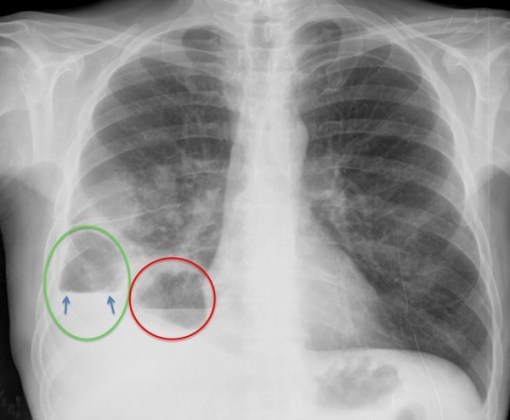

CASO: Febrícula y tos de 4 días de evolución.

Hallazgos:

- En la placa PA se observa una asimetría en los hilios pulmonares, el hilio izquierdo tiene una densidad aumentada.

- Tras examinar la placa lateral se observa un aumento de densidad en la columna que puede ser compatible con una condensación, es el signo de la desnificación vertebral.

SIGNO DE LA DENSIFICACIÓN VERTEBRAL: En la radiografía lateral normal, la densidad de la columna torácica tiende a disminuir desde la parte superior hasta el diafragma; la alteración de ese patrón por la presencia de una densidad superpuesta a la columna, indica la existencia de una consolidación pulmonar. Este signo adquiere especial valor cuando en la proyección posteroanterior la consolidación está oculta en el espacio retrocardíaco o en la base pulmonar.